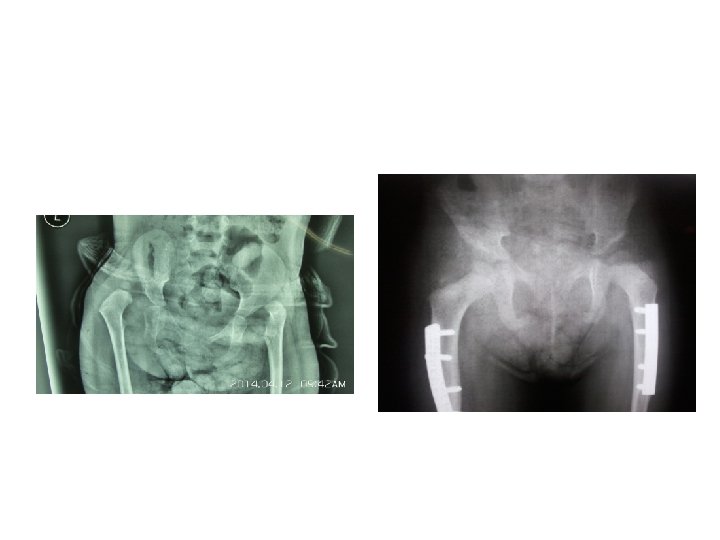

Imaging § Acetabular Index

Imaging § Acetabular Index < 30 wnl

Imaging